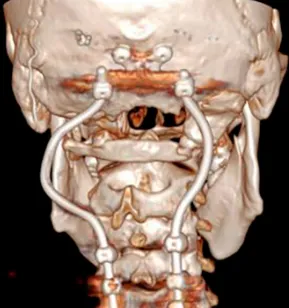

▼D:术后CT显示PMMA枕髁重建稳定良好。E:术后三维CT显示C0-C3-C4-C5枕颈融合稳定,与根钉弯曲有利于PBRT治疗。